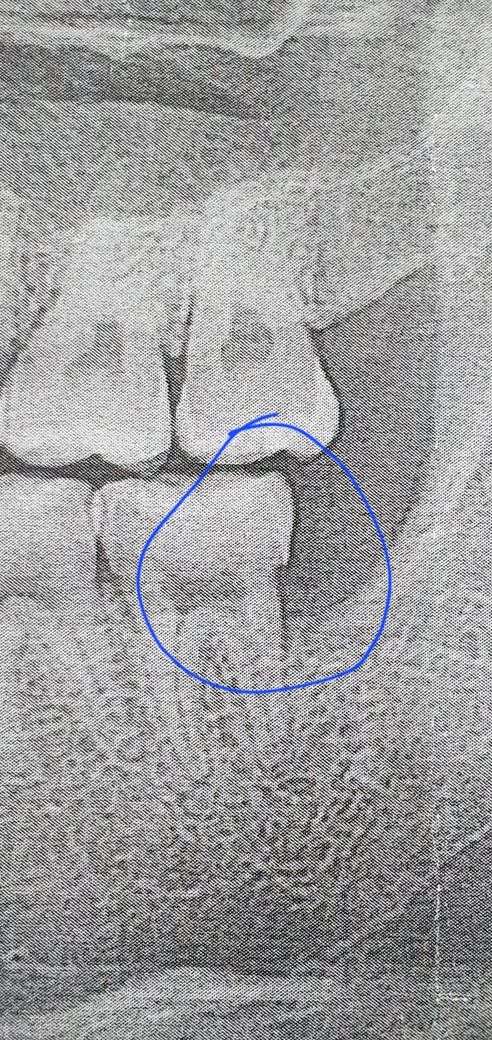

매복 사랑니 발치 후 어금니 패임 전후 사진 다시 올립니다

매복 사랑니 발치 미루다가 뽑았는데 앞 어금니 옆면이 사진처럼 각지고 부자연스럽게 패였습니다

전후 사진인데

• 3번 째 사진

치과의 실수로 해당 모양으로 된 것으로 보이진 않고 치아를 발치 한 후 겹친 모양이 드러난 것으로 보입니다.

• 사랑니가 기울어져 났을 경우에 사랑니가 걸려 있는 부위에 이물질이 남아 있게 되면 충치가 생기게 되고 사진처럼 각진 모양을 보일 수 있습니다 크게 문제가 되지 않기 때문에 걱정하지 않으셔도 되나 불편감이 있다면 해당 부위에 충치를 치료할 수 있습니다 자세한 확인을 위해서 치과에서 진료를 받아 보는 것을 권해 드립니다

• 손상이 일어날 정도로 겹쳐있진 않고 다만 사랑니와 어금니 틈 사이가 관리가 어려웠어서 충치가 생겨있는 것 같습니다 다만 해당부위는 깔끔하게 치료하기는 쉽지 않습니다 오히려 증상이 없다면 지켜보면서 관리를 잘해주는 것이 좋을 수도 있습니다